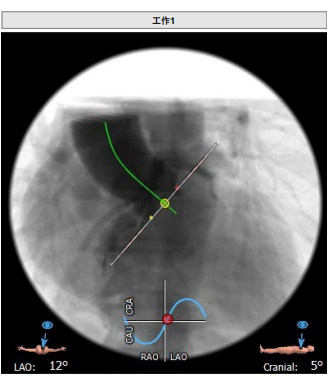

工作体位:LAO:12°CRA:5° ;左冠切线位:LAO:26° CRA:19°

患者为三叶瓣,左右、右无疑似粘连,瓣叶明显增厚,轻度钙化。右冠高度10.9mm,左冠高度9.5mm,冠脉高度均较低。法式窦小,心脏角度不大,左室大小可,升主动脉未见明显增宽,病人整体结构小,瓣环仅有16.9mm,左室流出道16.7mm,窦管结合部23.9mm,升主动脉31.4mm。选择右股作为主入路。

手术过程